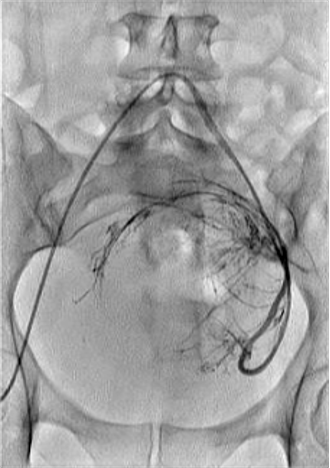

所有年龄超过 40 岁的患者, 卵巢受损 14%-43% 研究中闭经发生率(15%)与单纯UAE报告相似,可能与患者年龄(≥45岁)及卵巢储备自然下降有关。 ![]() 50岁,长期因子宫肌瘤导致月经出血过多,痛经和贫血。 子宫肌瘤栓塞术前,显示双侧子宫动脉发育不全,子宫肌瘤双侧卵巢动脉。 经皮股动脉穿刺双侧卵巢动脉栓塞,先500μm-700μm emboSphere 微球 术后4周,和6月的中短期随访,月经正常,子宫容积减少,贫血纠正,无卵巢功能衰竭。但看起来非灌注容积较少。 术后9月,由于子宫肌瘤持续存在,患者自己希望绝经,行全子宫和双侧卵巢切除术 术后病理,子宫内可见栓塞微粒伴有坏死,卵巢内也见栓塞微粒,但卵巢功能未受损。